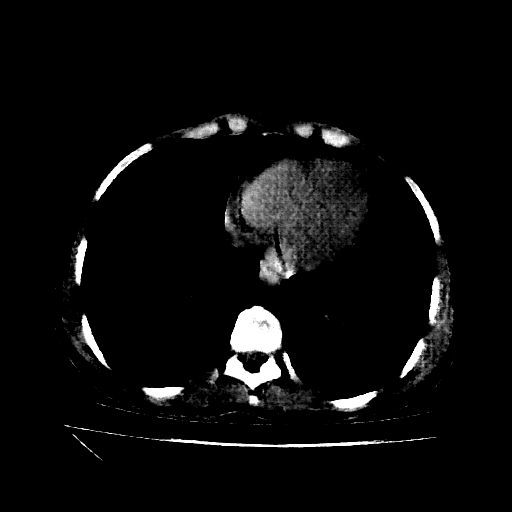

Original VENOUS CT scan

No window - Raw intensity values

Lung window (WL -600, WW 1500 β†’ Low βˆ’1350, High +150)

Mediastinum window (WL 40, WW 400 β†’ Low βˆ’160, High +240)